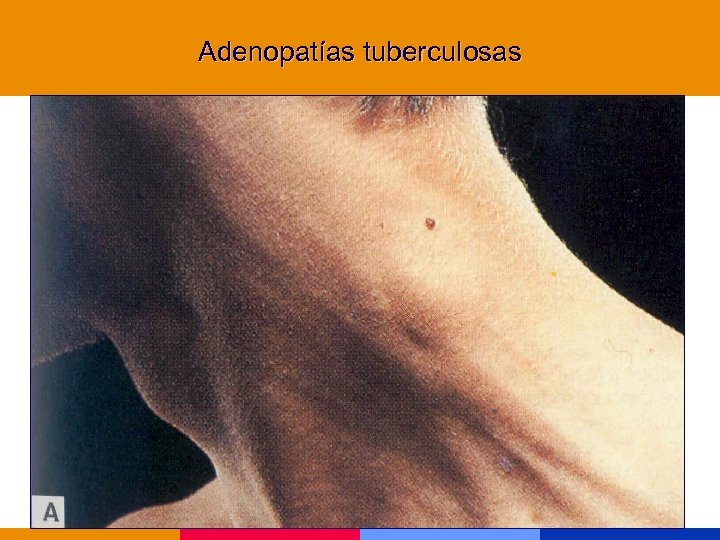

Adenopatías tuberculosas

Adenopatías tuberculosas